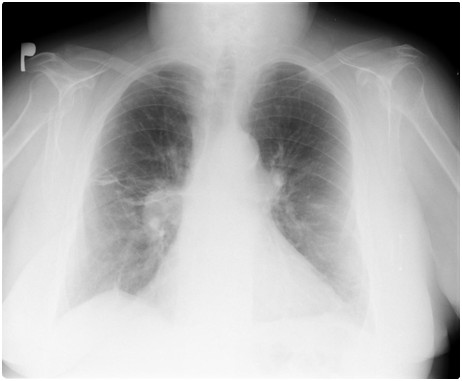

Do Poradni Chorób Płuc został skierowany przez lekarza rodzinnego 40-letni mężczyzna, niepalący, dotychczas nie leczony z powodu chorób przewlekłych. Powodem skierowania była postępująca od kilku miesięcy nietolerancja wysiłku fizycznego. Dwukrotnie w ciągu ostatniego roku był hospitalizowany z powodu infekcji oddechowej. Podczas hospitalizacji konieczne było prowadzenie wentylacji mechanicznej. W badaniach dodatkowych: FEV1 55%, FEV1%VC 85%, TLC 60%, PaO2 65 mmHg, PaCO2 50 mmHg. Rtg klatki piersiowej w załączeniu. U tego pacjenta:

Do Poradni Chorób Płuc zgłosiła się 55-letnia, otyła (BMI 38 kg/m2), paląca (30 paczkolat) kobieta. Powodem skierowania było omówienie wyników badania polisomnograficznego (PSG), które zostało wykonane z powodu występowania typowych dolegliwości towarzyszących obturacyjnemu bezdechowi podczas snu (OBPS). W PSG stwierdzono: AHI 5/h, średnia SaO2 podczas snu 86%, najniższa 70%. W badaniach dodatkowych: FEV1 70%, FEV1%VC 70%, PaO2 70 mmHg, PaCO2 49 mmHg. Rtg klatki piersiowej w załączeniu. Prawidłowe postępowanie to: